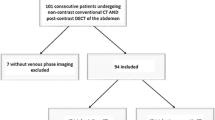

Patients

All patients who underwent abdominal CT between August and September 2001, and who had undergone a prior abdominal CT at our institution, were enrolled in this prospective study. As of August 2001, all CT studies were performed using a newly installed double-syringe power injector. Prior to this date, all studies were performed using standard single-syringe power injector. Our initial study population consisted of 53 patients who had undergone two abdominal CT studies, one without and one with saline flushing of the veins after contrast material injection. Informed consent for study protocol and dose of intravenous contrast material was obtained from all patients before each CT examination and the study was approved by our institutional review board. All patients fasted before the CT examinations. Patients with congestive heart disease (n=7) or ongoing chemotherapy during or between the examinations (n=5) were excluded from the study to avoid errors in measurement of contrast material enhancement due to change of cardiac output and progression or regression of fatty infiltration of the liver, respectively. The final study population consisted of 41 patients (24 men and 17 women; mean age 49 years, age range 27–86 years). The mean interval between the CT examinations was 153±93 days (range 6–372 days). There was no significant difference in body weight between the examinations (65.1±10.9 kg compared with 64.7±10.9 kg, p=0.13). Indication for abdominal CT were neoplasms of the gastrointestinal tract (n=13), primary liver tumors (n=10), neoplasms of the genitourinary tract (n=4), adenoma of the gallbladder (n=1), cholecystitis (n=1), choledocholithiasis (n=2), liposarcoma (n=1), Crohn’s disease (n=1), tuberculosis of the bone (n=1), abscess of the liver (n=2), pancreatitis (n=4), and diverticulitis (n=1).